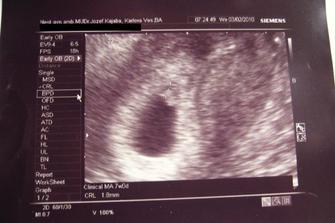

♥ 03.02.2010 sme boli u uja doktora a potvrdil nám vitalitu plodíku. Meriame 18mm a všetko je tak ako má byť. Vzali nám krvičku a o 10 dní ideme na ďalší kontrolný ultrazvuk